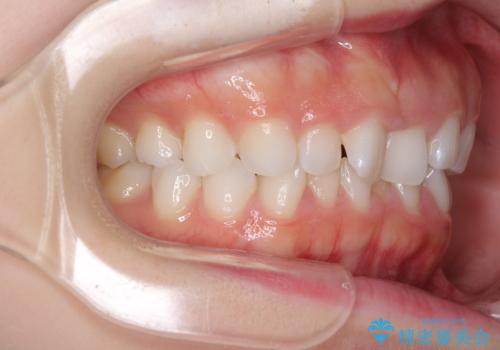

デコボコと深い咬み合わせの改善 インビザラインによる矯正治療

インビザラインによる上下歯列の拡大と、IPR(歯と歯の間を削る)にるスペースの獲得により、口元のデコボコとディープバイトを改善することとしました。

インビザラインは、装着していない時間がどれだけ短いかが、治療期間を大きく左右します。こちらの患者様は1日22時間以上、毎日欠かさず装着してくださったため、1年強という短期間で満足のいく歯列に整えることができました。